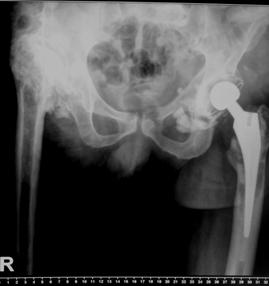

In aceasta lucrare au fost inclusi 35 pacienti, ce au suferit interventii de revizie a componentei femurale, in total efectuandu-se 38 de revizii. Din cei 35 de pacienti 13 au fost de sex feminin si 22 de sex masculin. Din figura nr. 2.2.1 reiese faptul ca 23 de interventii au fost realizate pentru revizia protezei soldului drept si 15 pentru revizia componentei femurale a soldului stang, existand o predominenta a interventiilor la nivelul soldului drept (12) in cazul sexului feminin

Fig. Nr. 2.2.1. - Repartitia pe sexe si lateralitate a interventiilor de revizie.